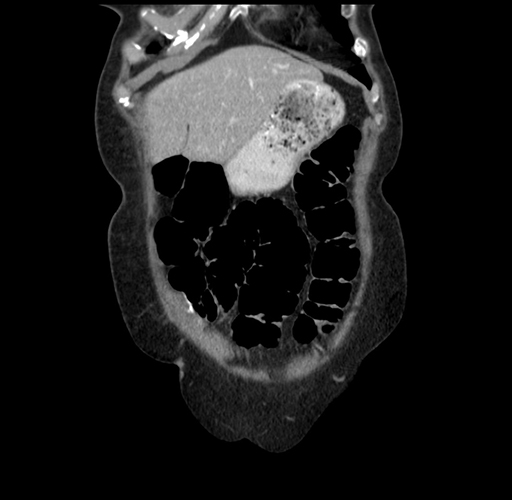

Pre-Chemo: Coronal Venous

Coronal Venous